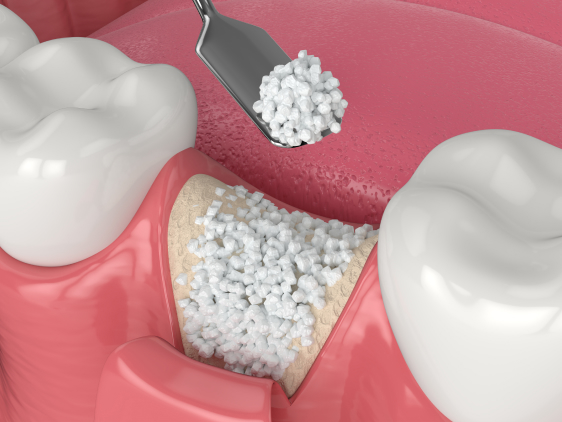

Crown Lengthening

A crown lengthening procedure involves reshaping gum tissue, bone, or both to expose more of a tooth. Crown lengthening is a common procedure for patients with a “gummy smile,” where excessive gum tissue around upper teeth makes teeth appear short. This treatment is also for patients who need to fix a tooth that broke off at or below the gumline, or to replace a filling or a crown that fell out. Crown lengthening exposes more of the tooth surface and allows your dentist to remove the tooth decay underneath or to place a crown.